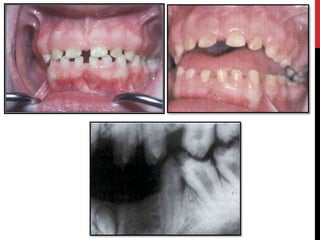

Amelogenesis imperfecta with taurodontism

(hypomaturation/hypoplastic AI)

 Combination of enamel hypoplasia with hypomaturation.

 Deciduous & permanent dentition involved.

 2 patterns.

 Extraoral radiographs  unerupted & sometimes spontaneously

resorbing teeth.

 Intra-oral radiographs  relative contrast b/w enamel & dentine in

cases where mineralisation may have been affected.